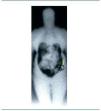

Figura 2. Gammagrafía de tórax anterior a los 40 minutos. En las imágenes precoces, refuerzo de captación patológico en hemitórax derecho.

Figura 3. Gammagrafía de tórax anterior a las cuatro horas. En las imágenes tardías se observa con claridad la captación patológica de hemitórax derecho, mostrando un aumento relativo de intensidad.